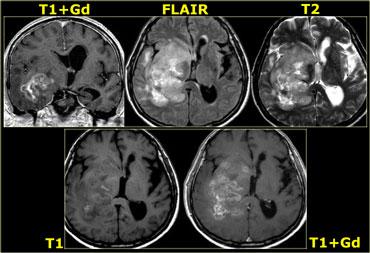

Bên trái là ví dụ về u nguyên bào đa dạng (GBM).

Sự ngấm thuốc cho thấy đây là khối u độ cao, nhưng chỉ một phần của khối u ngấm thuốc.

Lưu ý rằng còn có một thành phần nang với ngấm thuốc dạng vòng.

Các tế bào u có thể lan rộng vượt ra ngoài vùng phù não như thấy trên ảnh FLAIR.

Điều này là do u thần kinh đệm phát triển thâm nhiễm vào nhu mô não bình thường – ban đầu không có bất kỳ thay đổi tín hiệu MRI nào.

U nguyên bào đa dạng (GBM) với ngấm thuốc không đồng nhất và thành phần nang với ngấm thuốc dạng vòng

Ngấm thuốc không đồng nhất (dạng đốm) có thể thấy trong:

- Di căn não

- U ít nhánh (Oligodendroglioma)

- U nguyên bào đa dạng (Glioblastoma multiforme)

- Hoại tử do xạ trị